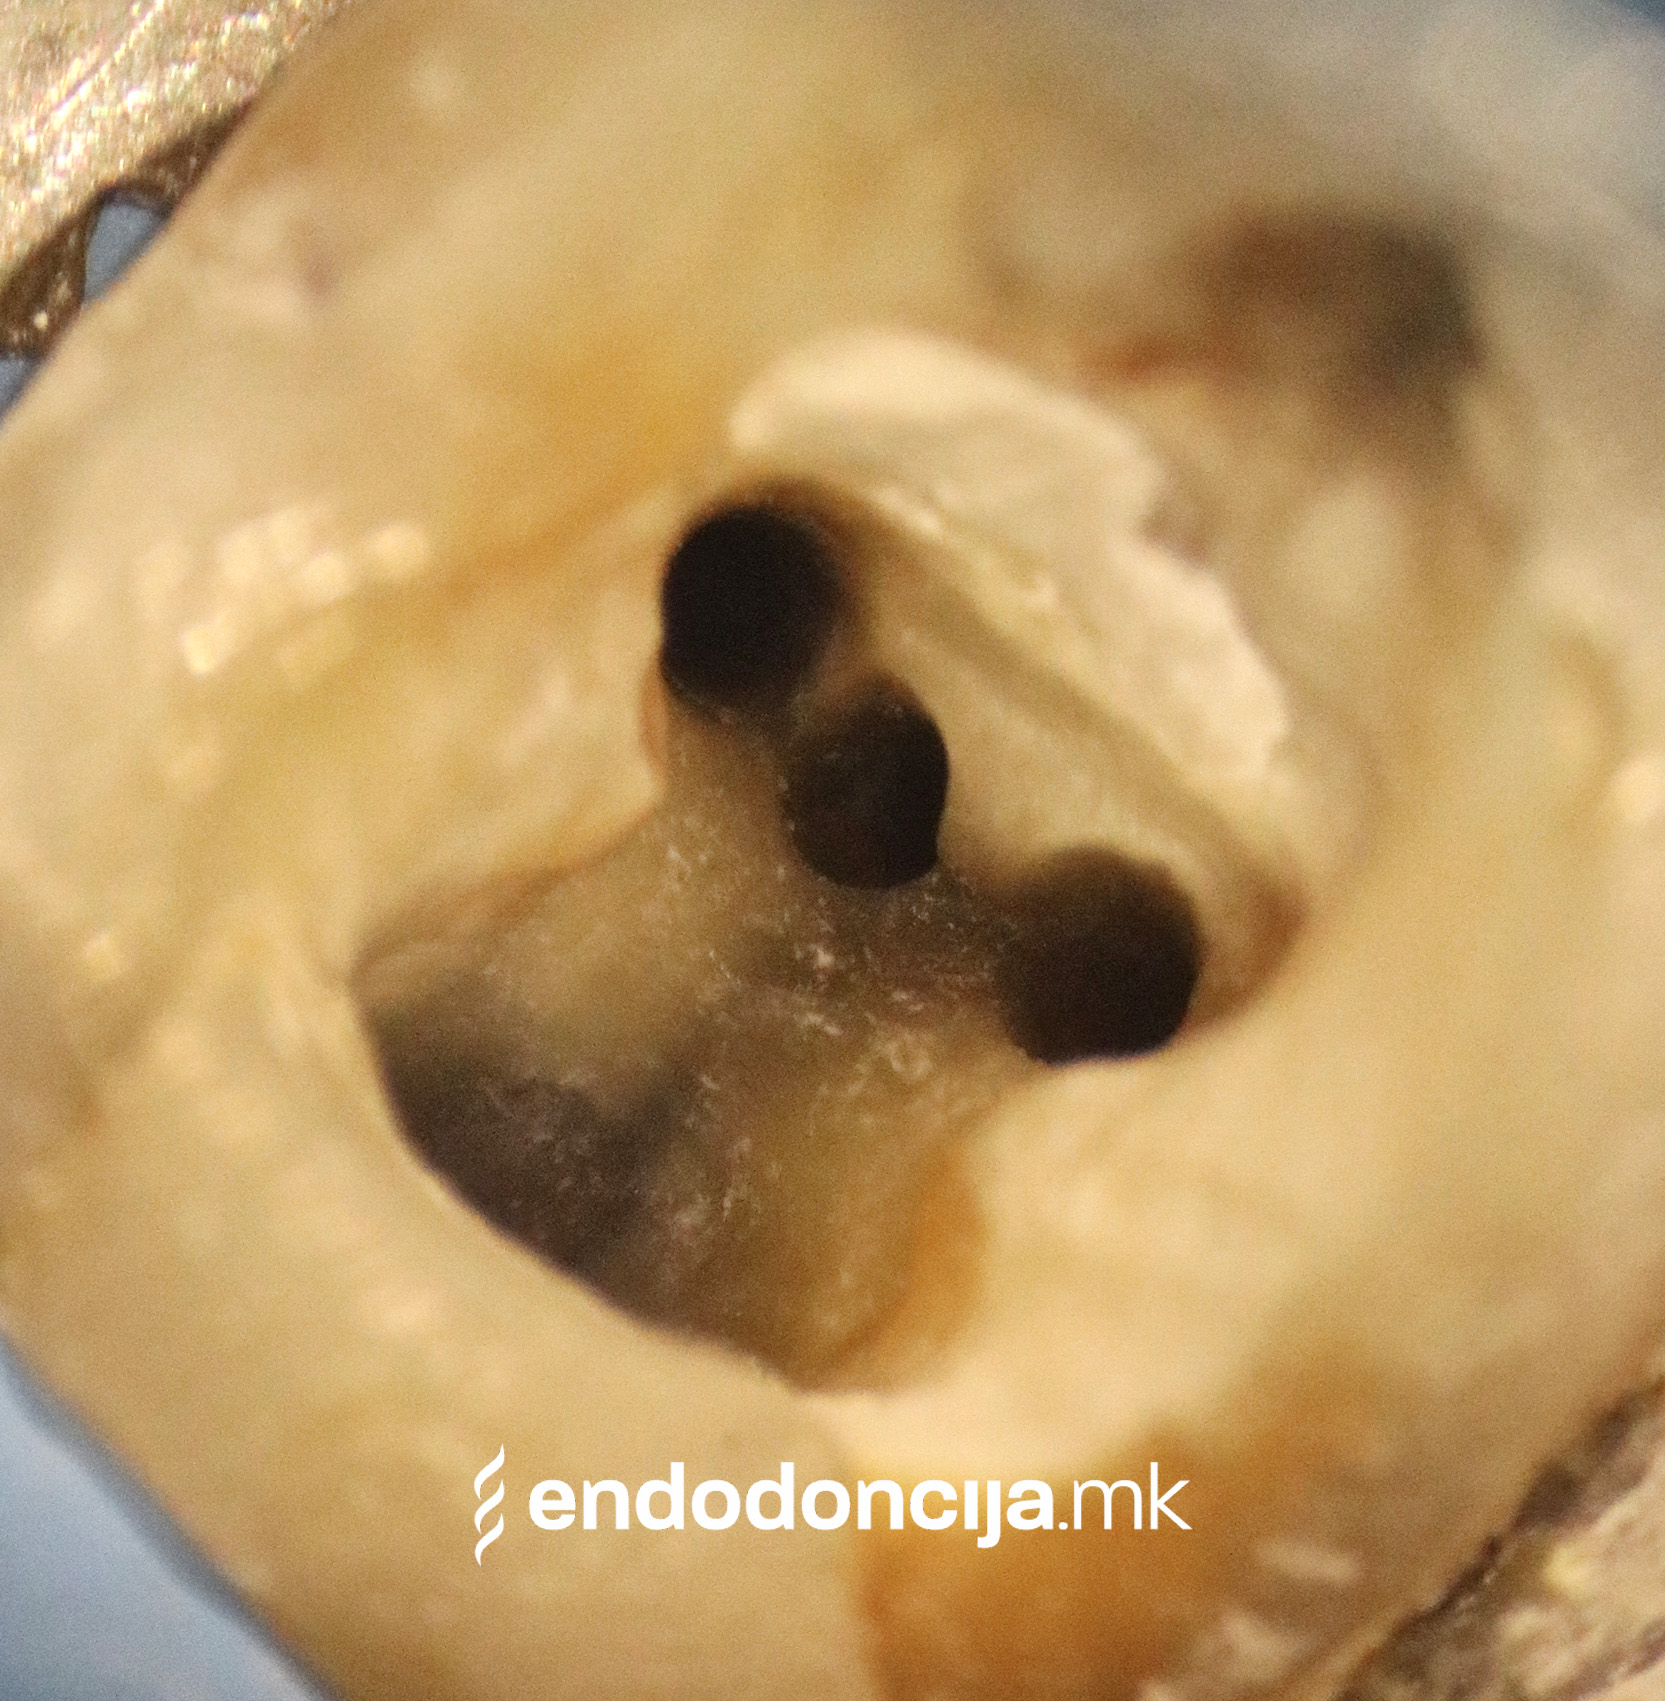

Она што е импресивно е прецизноста на микроскопските третмани. Дури и кога каналите се потешко достапни, може да се лоцираат и исчистат така што релапсите се со помала веројатност. Спротивно на тоа, скриените канали често остануваат неоткриени во конвенционалниот третман на коренскиот канал и затоа не можат да се чистат. Бактериите можат да се размножуваат таму без пречки и да предизвикаат воспаленија. Ова често останува незабележано со години додека не се појави забоболка, а со тоа и компликации.

Употребата на микроскоп исто така овозможува детектирање пукнатини или фрактури што може да предизвикаат болка или воспаление.